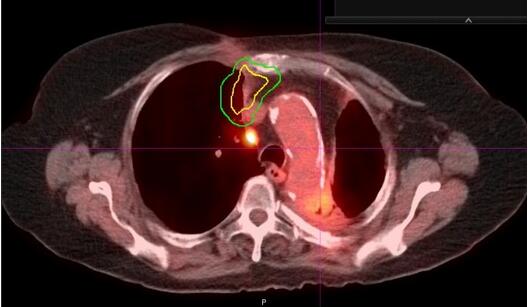

6年后,CT显示右上叶内侧有新发增强肿块,怀疑转移或新原发性肺癌(图2)。脑扫描显示转移疾病阴性。PET显示在预期区域有摄取和右肺门淋巴结有不确定的摄取(图3),但为阴性。 肺功能检查

图3